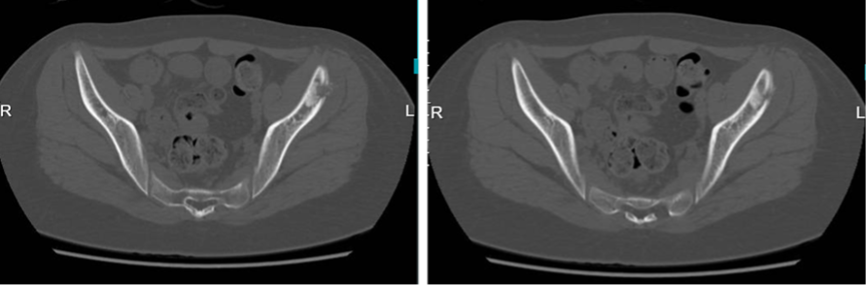

图:PET-CT提示:左髂骨骨质破坏伴低密度影葡萄糖代谢增高,考虑嗜酸性肉芽肿可能,建议结合病理